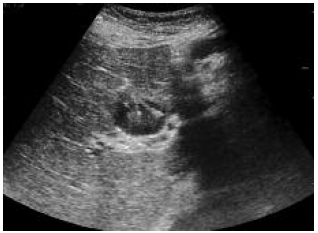

Figure 1. Ultrasound Shows Radiofrequency Prongs in the Periphery of Hepatocellular Carcinoma Nodule

Figure 2. During Radiofrequency Ablation, Nitrogen Gas Formation, Prevents Ultrasonography Visualization